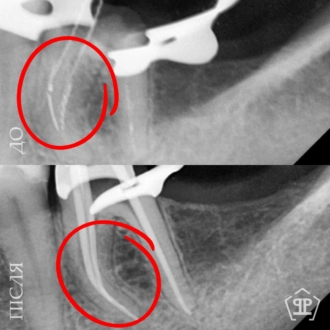

Во время диагностики обнаружен отлом фрагмента инструмента в корневом канале. Выполнено его безопасное извлечение, повторное перелечивание каналов, очистку и герметичное пломбирование.